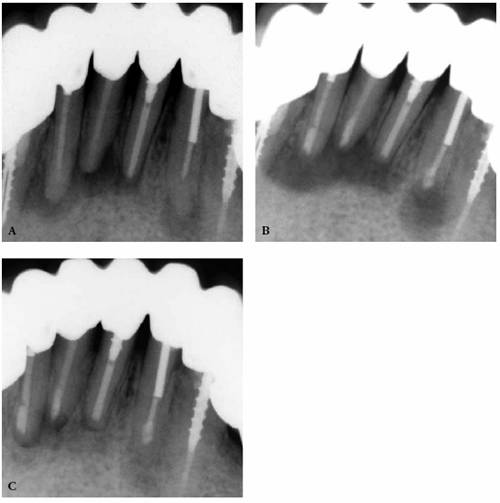

system as the root canal obturation material (Figures 19-53A

and B). In a

recent study, Ray and Trope evaluated the radiologic quality of both coronal

and canal obturations.24 It was demonstrated that a tooth with good

coronal and root seals had the best rate of absence of periapical lesions

(91.4%). Good restoration resulted in significantly less incidence of

periapical lesions than good endodontic filling (80% versus 75.7%). Poor

restoration resulted in significantly more periapical lesions than poor

endodontic fillings (48.6% versus 30.2%).

Figure 19-53A and B: (A) Thirty-five years after root canal therapy. The teeth are asymptomatic, and there are no radiographic changes. (B) Three years after distobuccal root resections and new castings. Periapical lesions developed around the mesiobuccal roots. During the extended treatment phase, the coronal ends of the silvers points were periodically exposed to saliva.